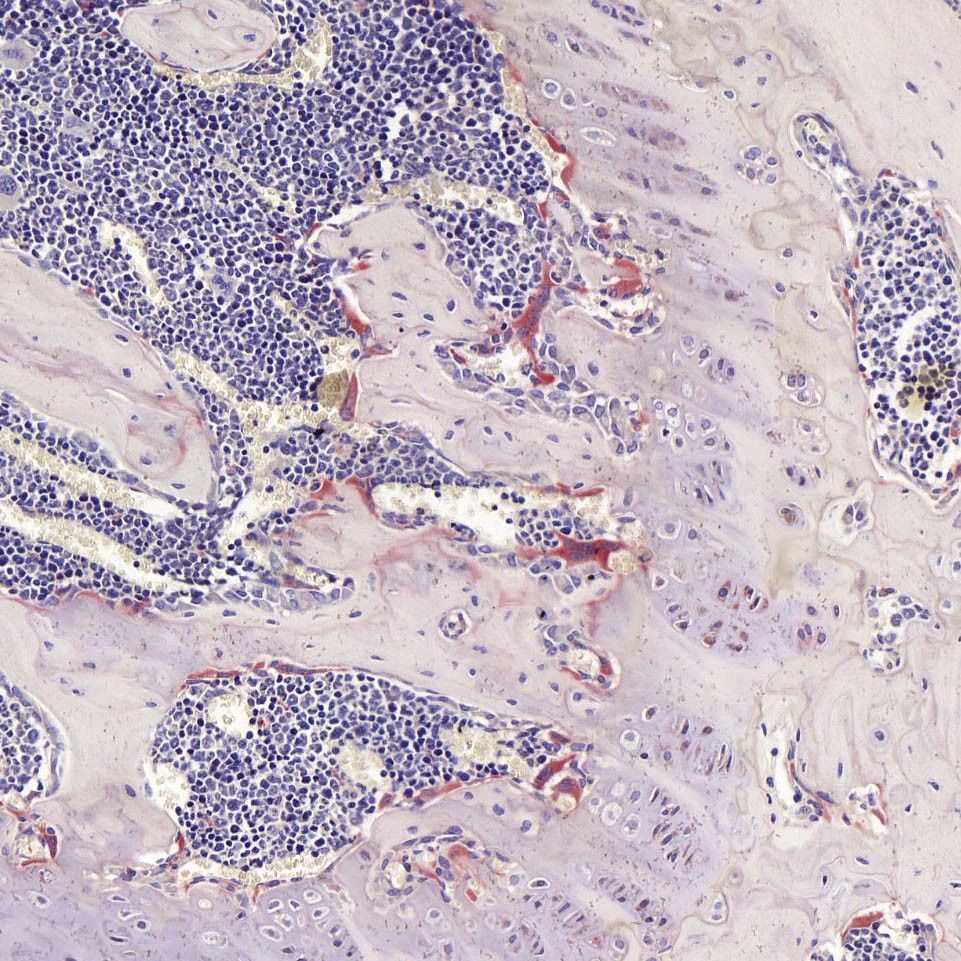

染色结果:

破骨细胞胞浆呈酒红色,核蓝色。

结果展示

结果判读:

破骨细胞呈酒红色或浅红色,细胞核呈浅蓝色